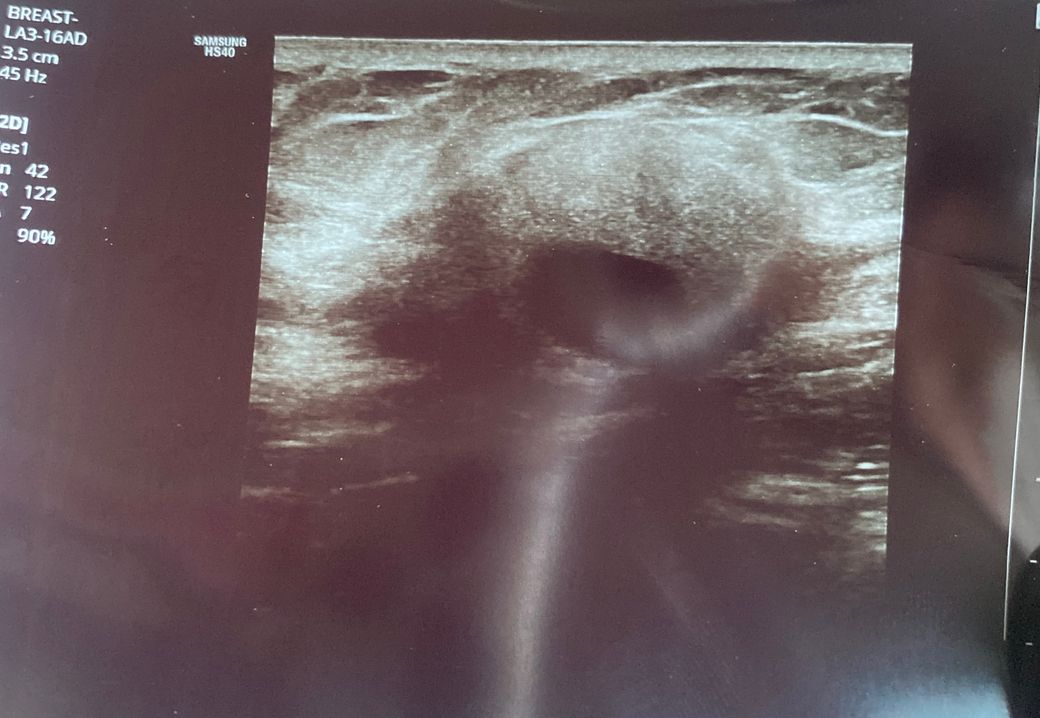

오른쪽 쇄골뼈 아래 바깥쪽에 딱딱한 혹이 생겨 병원에 갔습니다. 한 병원에서는 모양이 예뻐 암 가능성은 없다고 했지만 다른 병원에서는 모양이 일반적이지 않다고 조직검사를 했습니다. 조직검사 결과는 다음주에 나오는데 마음이 너무 불안하고 힘들어서 잠을 잘 수가 없습니다. 이런 모양은 주로 어떤 암의 양상일까요. 참고로 혹이 아프지 않습니다.피부에 검은 점도 없구요..

모양 자체가 불규칙적이지는 않기 때문에 양성의 가능성도 높지만 우선 조직검사 결과를 기다려 보시고, 필요시는 MRI등의 검사도 시행해 보시는 것을 추천드립니다.